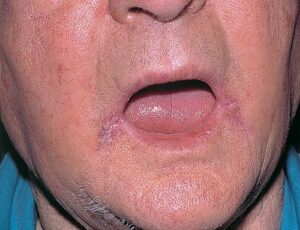

Angular cheilitis= التهاب الشفتين الزاوي

Angular cheilitis

Angular cheilitis (also referred to as perleche) manifests as an inflamed lesion on the mouth. It can also look like chapped lips. It can be caused by many things including bacteria, fungus, malnutrition, or by an intolerance to a certain type of yeast called candida albicans. This intolerance can lead to a fungal infection that is called candidiasis.